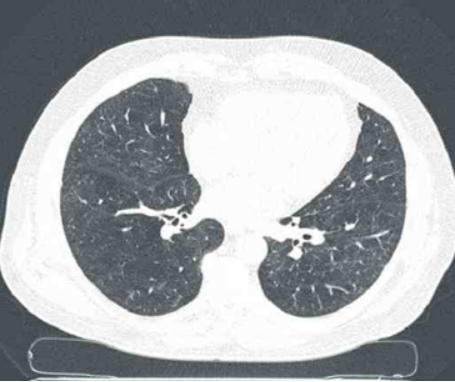

2. EIT与CT的互补性

CT和EIT在应用中各具优缺点,但也有一定的互补性(表1,图2,视频1)

图片

2  CT解剖成像显示含气组织

视频1  EIT功能性呈像:显示气体进出变化的区域

EIT通过不同分区方式可将肺部分为多个感兴趣区(ROI): 一种是纵向划分, 包括ROI 1腹外侧、ROI 2腹内侧、ROI 3背内侧和ROI 4背外侧; 另一种是象限划分, 包含ROI 1右上区、ROI 2左上区、ROI 3右下区和ROI 4左下区。